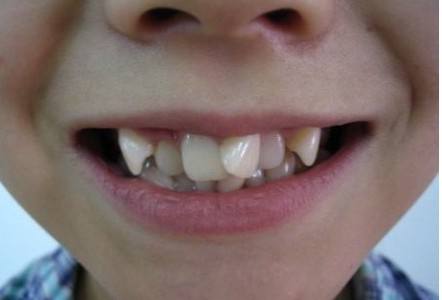

毕竟牙齿长成下面这样,再加上小伙伴三言两语的小绰号,日积月累宝宝们自然是难以开怀大笑了。

作为儿童成长关爱协会会长,WORD姐深8了一下,发现引起宝宝牙齿不齐的因素真不少!先天因素我们管不着,但后天不良习惯可以加以预防!譬如这些: